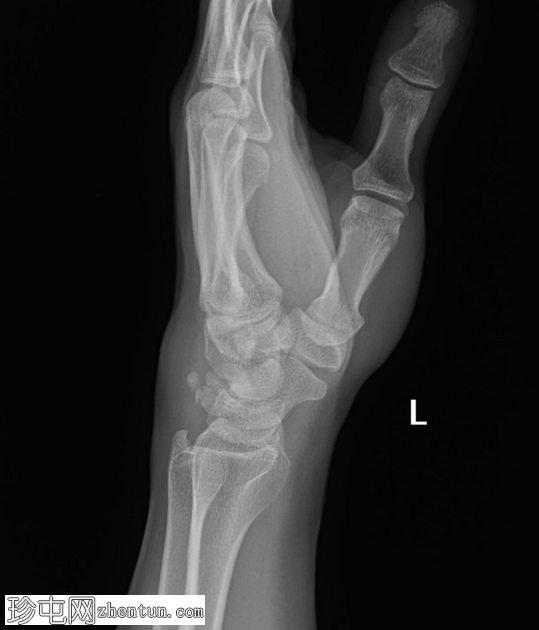

正位片

侧位片

左腕关节正位和侧位X线片显示三角骨撕脱性骨折,仅在侧位片上可见,放大锐化后骨折线显示更清晰。